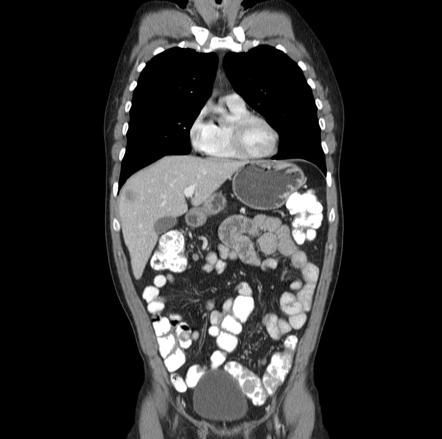

Turcot syndrome is also known as a brain tumor – polyposis syndrome or glioma – polyposis syndrome. It is a genetic disease characterized by adenomatous polyps in gastrointestinal tract and brain tumors. Individuals with Turcot syndrome present with diarrhea, bleeding per rectum, abdominal pain, and weight loss attributed to tumors in gastrointestinal tract. Neurological symptoms secondary to brain tumors are also present. On physical examination, café au lait spots and lipomas may be present. basal cell carcinoma may also be associated with Turcot syndrome. Reference: https://rarediseases.org/rare-diseases/turcot-syndrome/ Image via: https://radiopaedia.org/articles/polyposis-syndromes